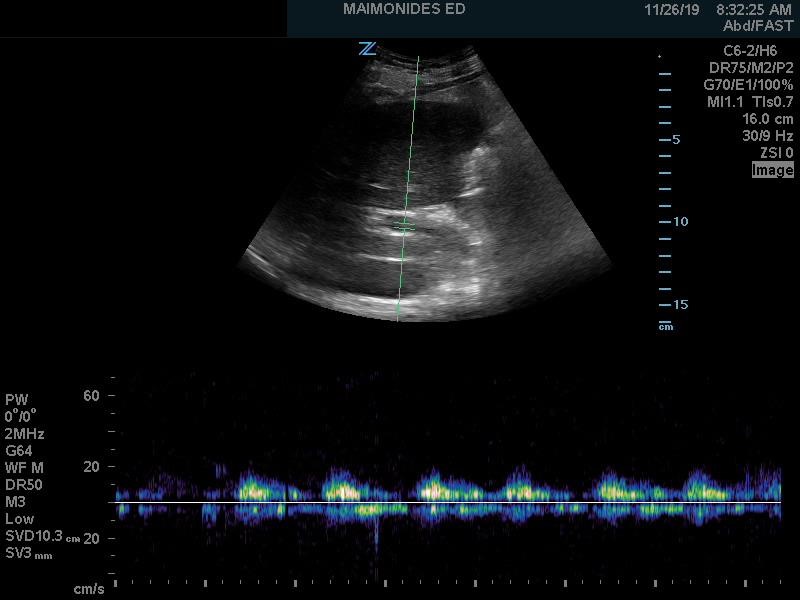

Figure 5. Renal Vein Doppler with normal flow6

(Reproduced with permission)

Venous flow is seen underneath the baseline and is continuous (normal)

Conversely, renal venous flow remains a more specific marker for renal vein congestion and renosarca as it allows us to assess venous congestion within the venous system itself. As right atrial pressures increase, similar in nature to the hepatic vein, the normal continuous intra-renal venous doppler pattern (Figure 5) transitions to an interrupted biphasic pattern (Figure 8A), and ultimately to a primarily diastolic venous flow pattern (Figure 8B). This remains physiologically similar to our understanding of the hepatic venous waveforms: as right atrial pressures rise; the systolic venous flow will gradually decrease until a primary diastolic venous flow is present. At this point, the venous system loses its ability to compensate for increased fluid. When compared to hepatic venous flow, renal flow provides two major advantages: an ability to easily determine systolic and diastolic flow and being more specific to renal venous congestion.